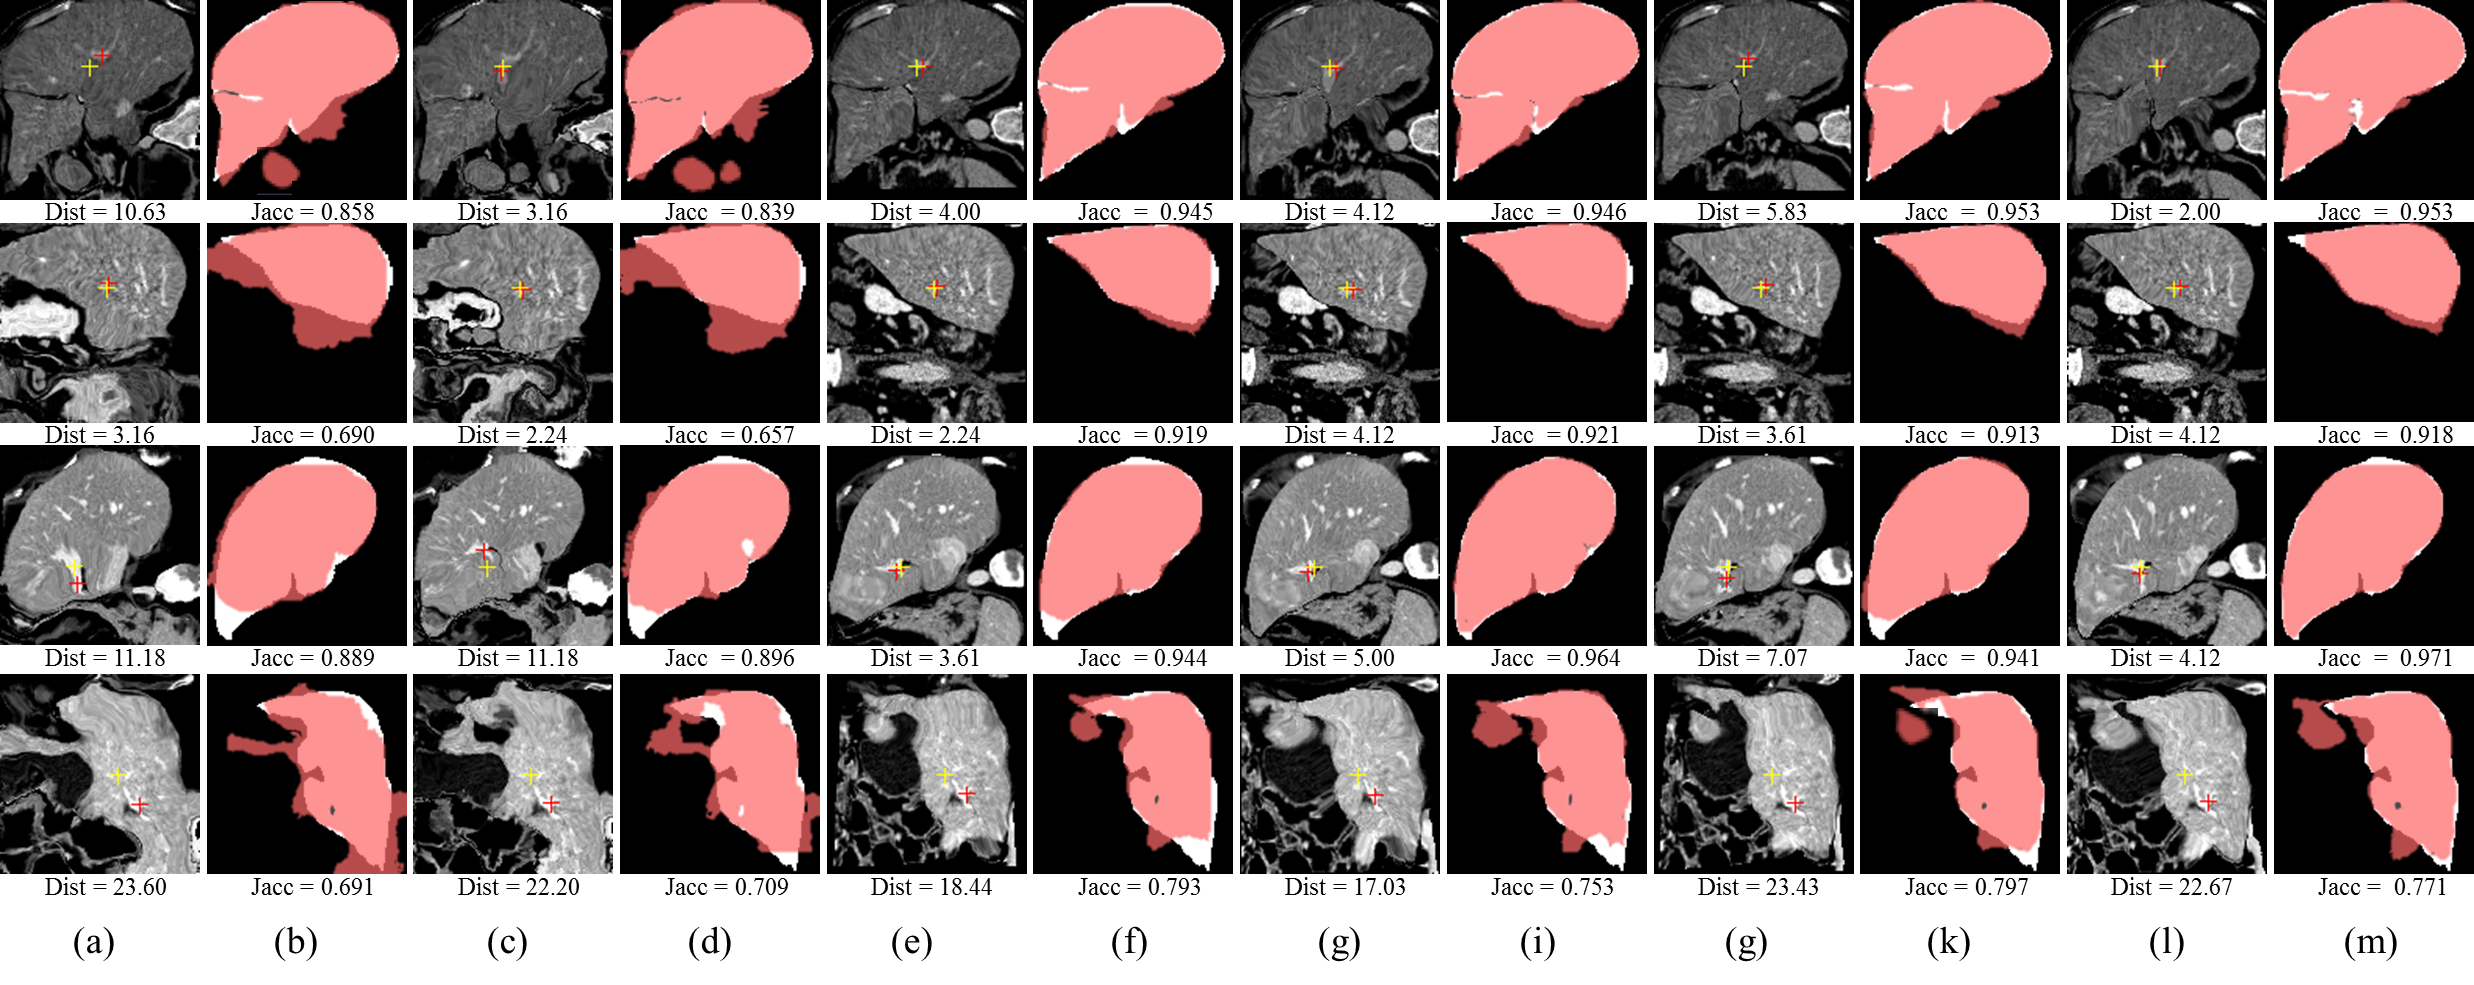

Refer to caption

Figure 7: Illustration of the liver registration performance of the proposed unsupervised methods, our best supervised baseline (w/ mask) methods and one the best traditional registration algorithms (Elastix) with the best Dist: (a) Moving image, (b) Ground truth segmentation mask of moving image, (c) Fixed image, (d) Ground truth segmentation mask of fixed image. (e), (g), (i) and (k) respectively denote the moving images warped by the best traditional registration algorithm (elastix), our best supervised baseline method (itk16), our best unsupervised method PN. The translucent red masks in (f), (h), (j), (l) respectively correspond to (e), (g), (i), (k) and denote the warped ground truth segmentation mask of the moving images. The white masks in (f), (h), (j), (l) are the ground-truth segmentation mask of the fixed image. The red and yellow crosses denote landmarks of moving image and fixed image, respectively. Dist in (c) and Jacc in (d) denote no registration.